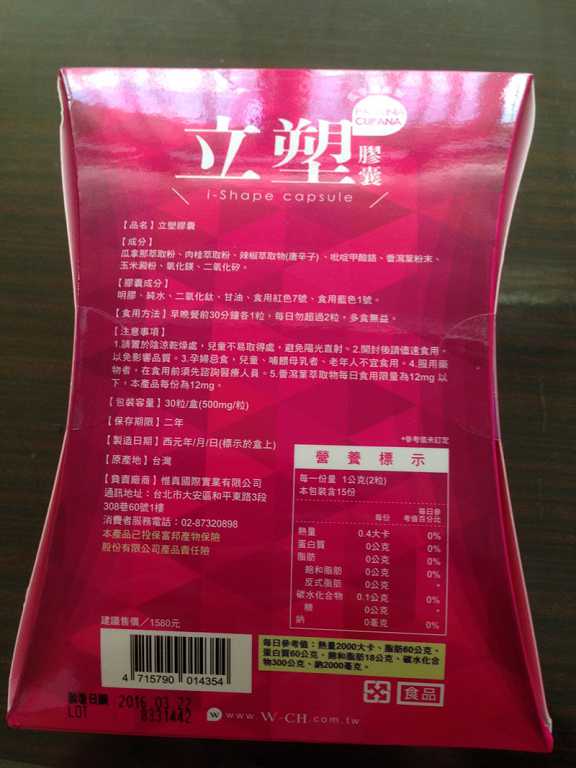

Supercut塑魔纖立塑膠囊的成分有:瓜拿那萃取粉、肉桂萃取粉、辣椒萃取物(唐辛子)、吡啶甲酸鉻、番瀉葉粉末、玉米澱粉、氧化鎂、二氧化矽。

食用方式:早晚餐前30分鐘各1粒,每日不超過2粒。(多食無益)

番瀉葉萃取物每日食用限量為12mg以下,